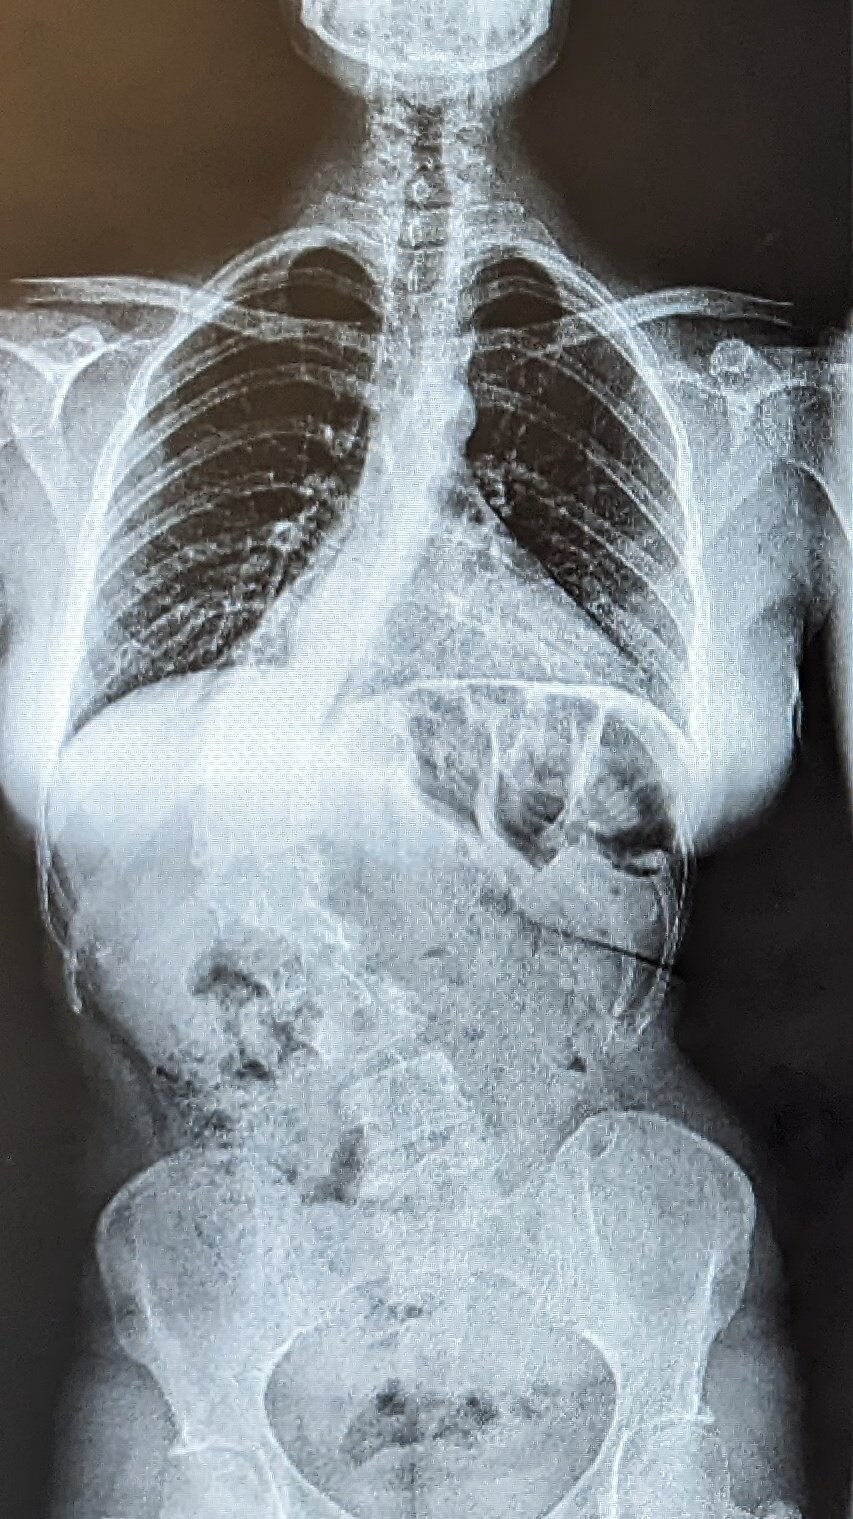

척추측만증 수술 전과 후 Anonymous | 2025.10.18 15:02 | 조회 12 https://qquing.net/bbs/board.php?bo_table=humor&wr_id=1669205 주소 복사 이전글 다음글 랜덤 만화 목록 본문 척추가 저렇게 휘어쓰면 얼마나 고통스러울까 추천 0 비추천 0